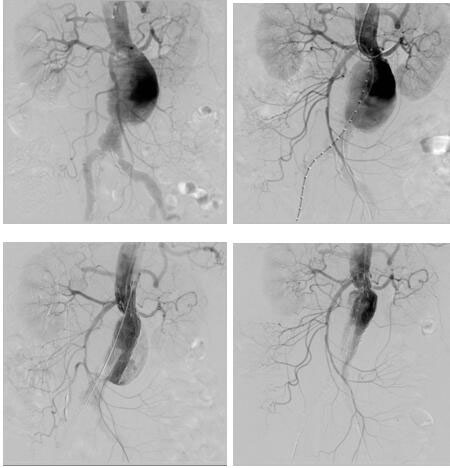

日前,血管介入科为一位患肾下复杂型腹主动脉瘤(左肾动脉距离瘤体仅4mm)74岁老年女性完成肾动脉烟囱+腹主动脉瘤覆膜支架腔内隔绝术,术后恢复良好。该患者基础疾病多,已经出现腹痛症状,腹主动脉瘤瘤体随时有破裂风险,但左肾动脉距离瘤体仅4mm,采取传统开放手术(腹主动脉瘤切除+Y型人工血管置换+左肾动脉转流术)手术创伤大,手术风险高,经血管外科治疗团队反复研究病例,并在院领导支持下,决定采取腔内治疗:先经肱动脉穿刺置鞘于左肾动脉留置导丝,再经双侧股动脉上导丝导管造影定位,在施放腹主动脉主体支架前先经左肱动脉留置导丝导引下于左肾动脉置入VIABAHN支架保证左肾动脉供血,再释放腹主动脉主体支架,解决了左肾动脉距离瘤体过近的问题。该例手术的完成,标志着我院在腹主动脉瘤的腔内治疗跨入省内领先行列。